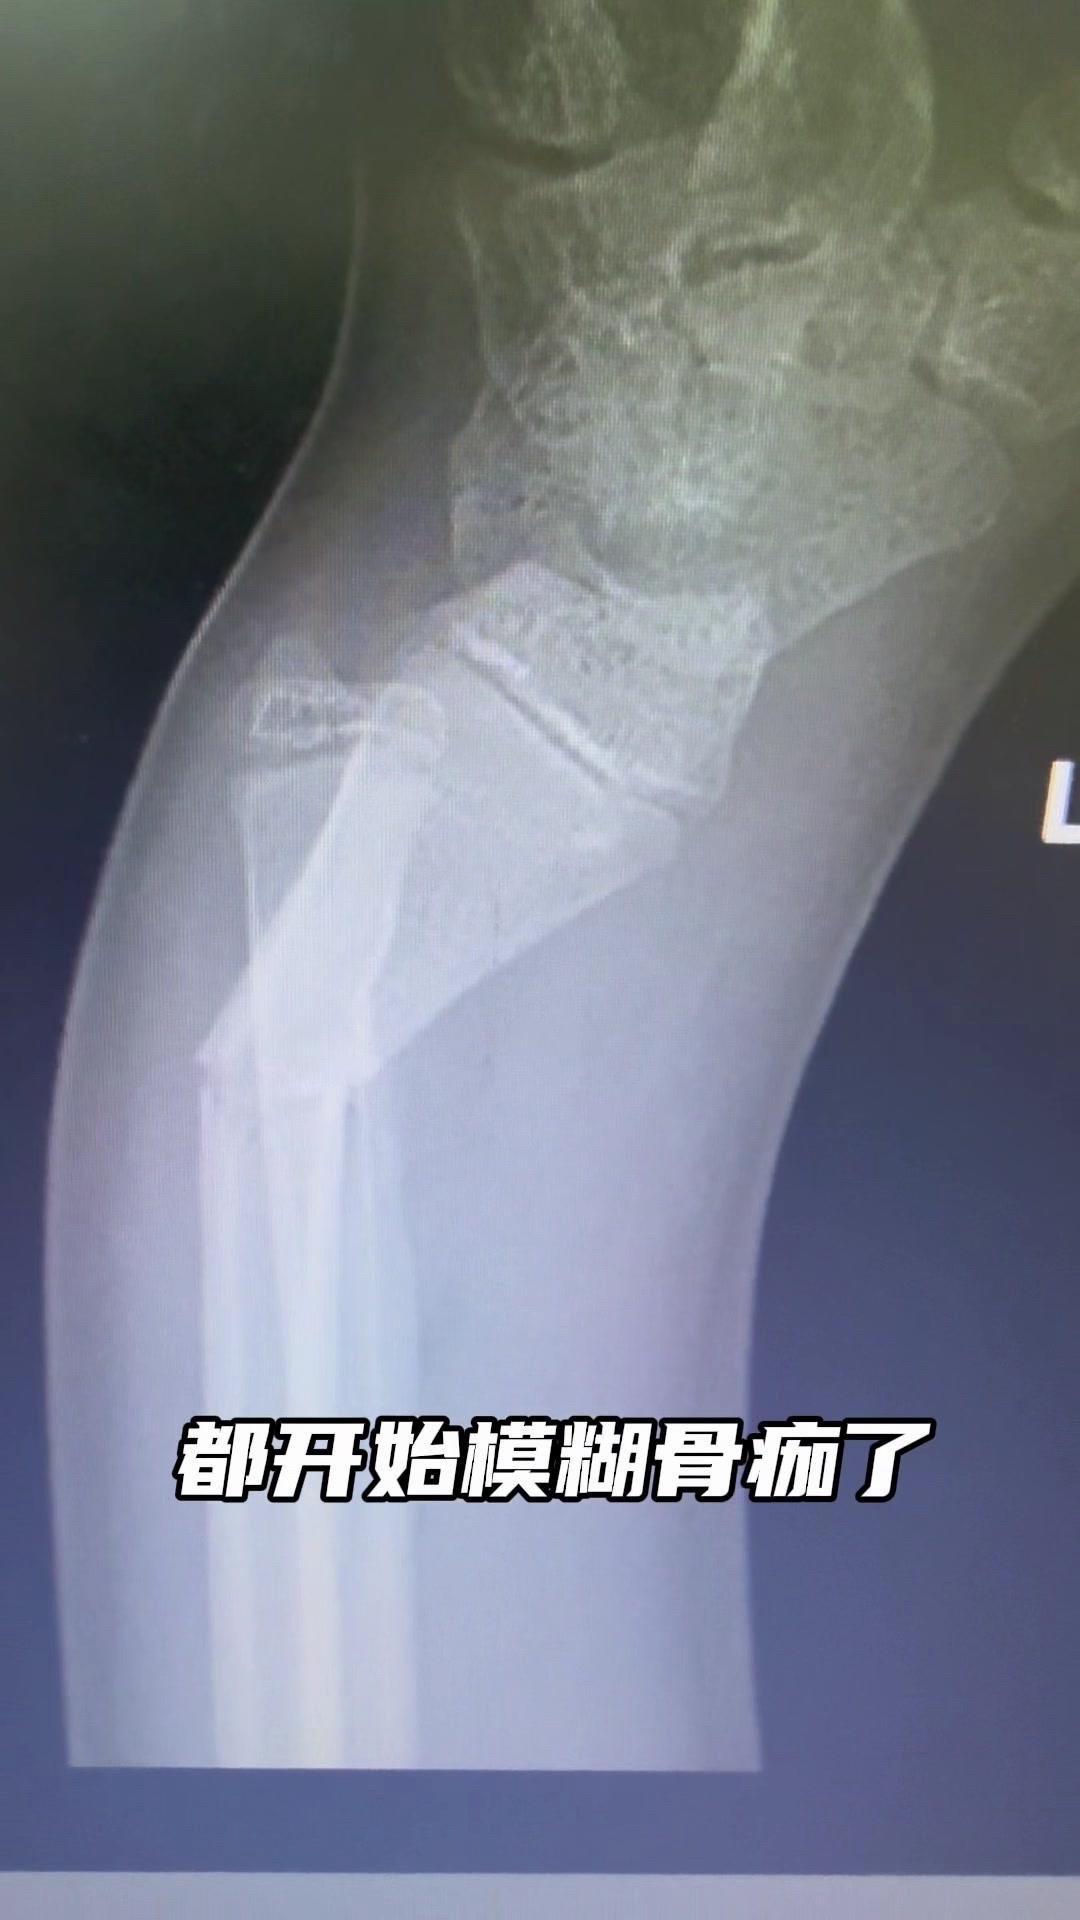

儿童骨折别拖延!💡上周接诊一个10岁女孩,摔了一跤后腕部疼痛还伴有畸形,家长觉得是小伤没在意,结果一周后孩子疼得更厉害,畸形也更明显了。来医院拍片一看,妥妥的骨折,而且才一周就开始出现模糊骨痂,掌区还有45度左右的成角畸形。家长这才意识到问题严重性,其实孩子受伤后出现疼痛、畸形,哪怕看起来不严重,也得及时检查,别让小问题拖成大麻烦。